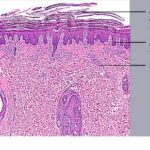

PATHOLOGY

Pathologic findings in pityriasis rubra pilaris vary according to the duration of the disease. The findings are most likely to be diagnostic in the acute phase, when hyperkeratosis, acanthosis with broad short rete ridges, and alternating orthokeratosis and parakeratosis oriented in both horizontal and vertical directions can be observed (see Pityriasis Rubra Pilaris At a Glance). Usually, there is a sparse superficial, perivascular lymphocytic infiltrate in the underlying dermis. Keratinous plugs of the follicular infundibula as well as perifollicular areas of parakeratosis may also be present. A prominent granular layer and dilated, but not tortuous, capillaries are features that help to distinguish pityriasis rubra pilaris from psoriasis, the most important differential diagnosis.